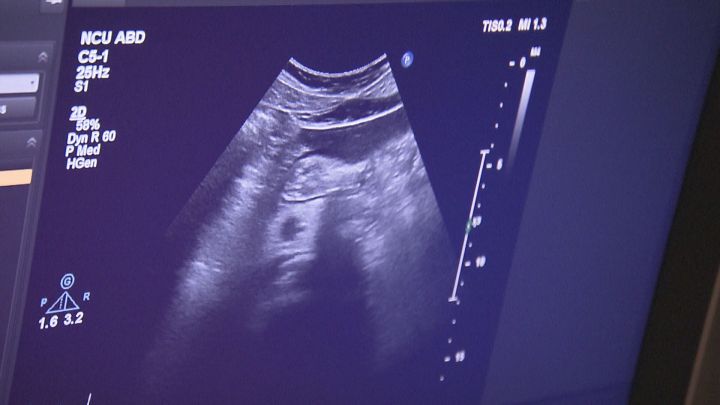

ゼリーをつけたお腹に超音波を出す機械を当てて、体の中を見ていきます。

「今これは腎臓が映っていますね。腎臓と肝臓の色合いがそこまで変わらないということで、脂肪肝があると肝臓がもっと白く映りますので脂肪肝なし」

検査にかかる時間は20分ほどです。加藤晃久助教によりますと、体への負担がほとんどなく、肝臓、すい臓、腎臓、胆のう・胆管など、多くの臓器を一度にみられるのが大きなメリットです。